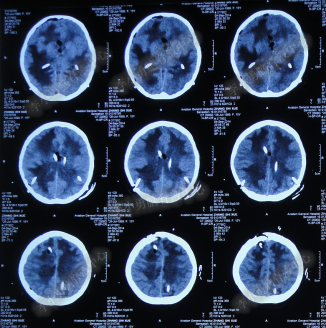

第3次手术右侧脑室外引流术后1个月时间内,脑积水仍没有得到控制,再给予腰大池引流,期间多次试图拔除右侧脑室外引流管(多次调高脑室外引流管的高度),但因患者意识变差,而无法拔除引流管,给予拔除腰大池引流,治疗期间曾多次查头部CT均示脑积水仍无改善(图-20、图-21、图-22、图-23)。

图-20:2014年7月24日头部CT

图-21:2014年7月29日头部CT

图-22:2014年8月4日头部CT

图-23:2014年8月15日头部CT